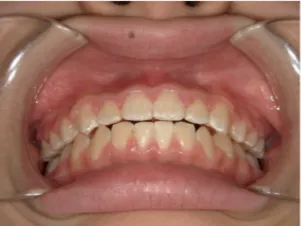

治療中④中1:治療中 マルチブラケット法へ移行

*マルチブラケット法移行前

*マルチブラケット法移行後